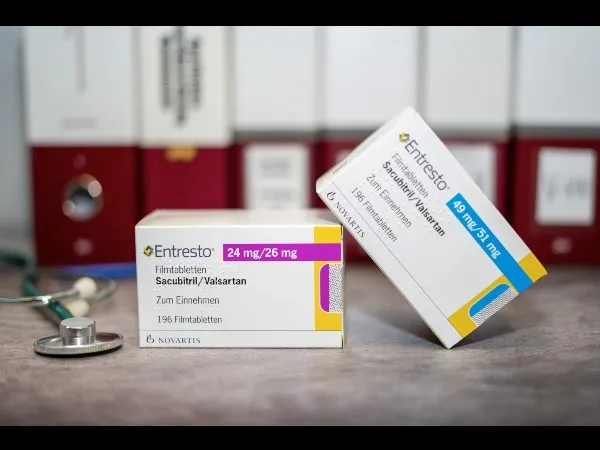

Uso do Sacubitril/valsartana vs iECA/BRA na diálise: o que temos de evidência?

Uso do Sacubitril/valsartana vs iECA/BRA na diálise: o que temos de evidência?Sacubitril/Valsartana vs. iECA/BRA na Diálise – A metanálise mais recente traz luz sobre o impacto dessas terapias em pacientes dialíticos. Descubra o que a ciência revela para a prática nefrológica!

Luís Sette

2 anos atrás